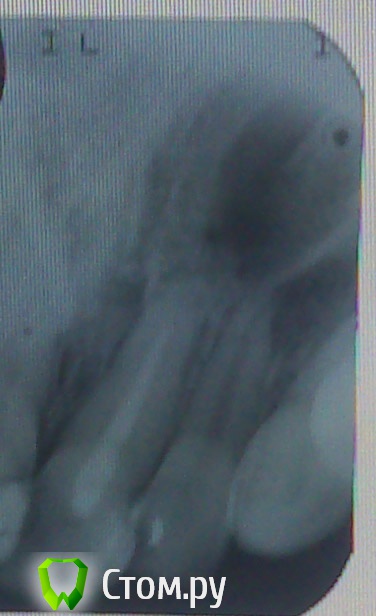

MaksimAleks Опубликовано 1 августа, 2014 Автор Поделиться Опубликовано 1 августа, 2014 Большое спасибо за внимание к моей проблеме. К сожалению, лучшее качество и ортопантомограмма в данный момент недоступны. Но исходя из нового прицельного снимка все таки киста 21? К нормальному стоматологу смогу попасть только через неделю. Насколько мне позволяет изучение данной тематики, это произошло из-за недопломбировки канала, но как только мне её произвели, уже было покраснение десны и через пару дней воспаление.Возможно ли такое быстрое развитие (киста была на зубе с живой пульпой)? А может всему виной его сосед 22, который уже как 9 лет депульпирован и на снимке имеет либо не запломбированный канал (как такое могло произойти в частной стоматологии) либо не контрастный материал? По виду он даже за эти десять лет почти и не изменился, в отличие от сильно потемневшего 21-го. В тоже время во время нагноения кисты чувствовалось давление на 22 сверху, быть может потому, что киста 21-го над ним?Через какой промежуток времени мне стоит обратится за имплантацией? Ссылка на комментарий

shishok Опубликовано 1 августа, 2014 Поделиться Опубликовано 1 августа, 2014 А может всему виной его сосед 22.Скорее всего.Лечение 21 без перелечивания канала в 22 бесполезно.Лечите оба зуба обязательно. Ссылка на комментарий